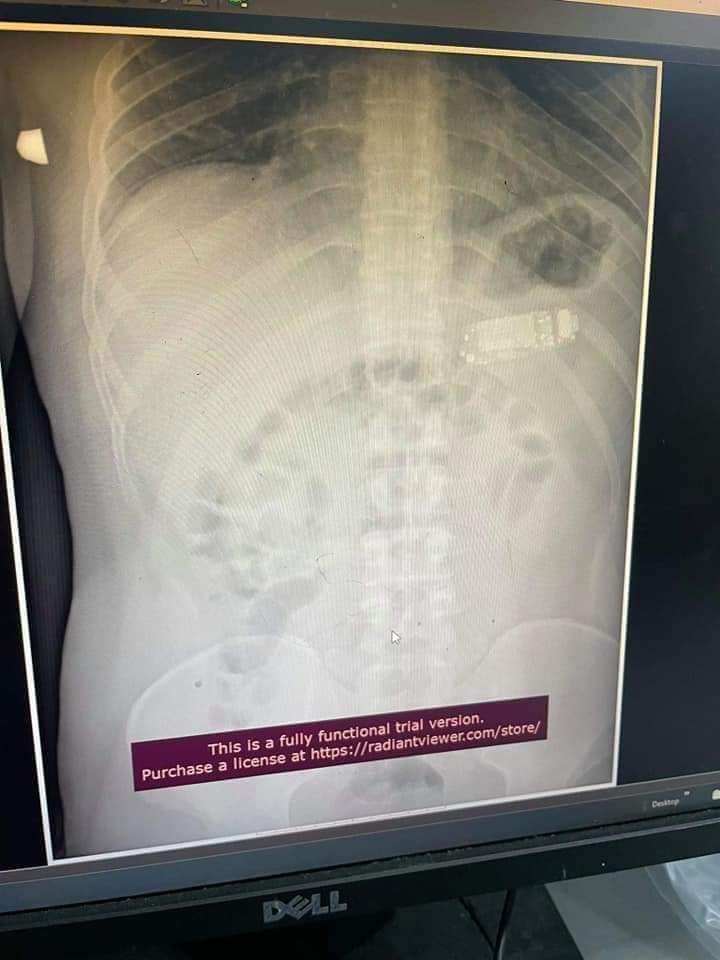

Postimi i tij i plotë: NXJERRJA E TELEFONIT NGA STOMAKU Mashkulli 33 vjec para 4 ditesh kishte perbire nje telefon te vogel. Me rruge endoskopike, pra pa e prere lukthin, nxorrem telefonin e ndare ne tri pjese. Pa komplikime.